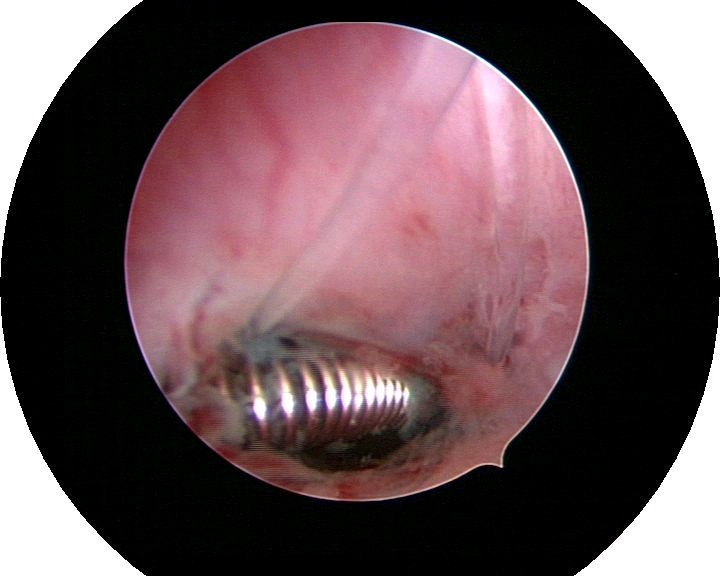

患者35岁,G4P0,2011年4月因继发不孕、月经减少2年,行宫腔镜探查,发现宫腔广泛重度粘连,单极电切分粘,恢复宫腔形态,显露双侧输卵管开口,放置节育环一个,术后月经恢复正常。2011年9月行宫腔镜二探并取环,O型环部分嵌顿,分离残留粘连,宫腔形态正常,双侧输卵管开口可见,同时行腹腔镜下左侧卵巢囊肿剥除术,术中通液双侧输卵管通畅。术后病人及爱人外出旅行,2个月后自然妊娠至足月,2012年7月要求我到其住院医院为其剖宫产,胎盘粘连,出血较多,手术顺利。现49岁,G5P1。